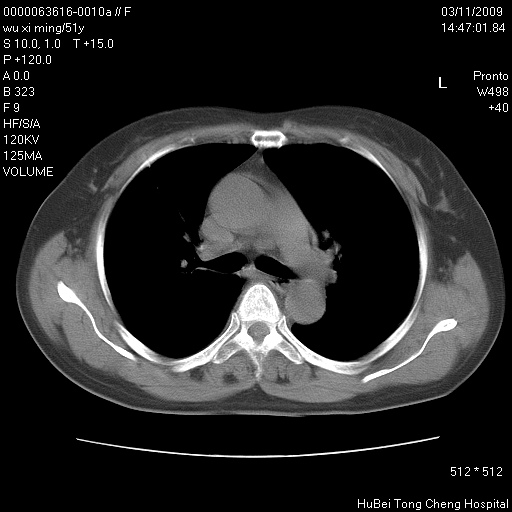

患者 女,51岁。因“胆囊炎,胆囊结石”,行常规术前胸部x线检查发现:右上肺结节病灶,建议行进一步检查。患者无咳嗽、咳痰及咯血等呼吸道症状,近期出现背部疼痛不适。

胸部ct轴位平扫(层厚10mm,螺距1.5,重建间隔10mm;部分层面:层厚3mm,螺距1.0,重建间隔3mm),图像如下:

右肺周围型肺癌伴肺内转移信胸椎转移

支持--右肺周围型肺癌---胸椎转移

右肺周围型肺癌伴肺内转移及胸椎转移。已无手术机会。